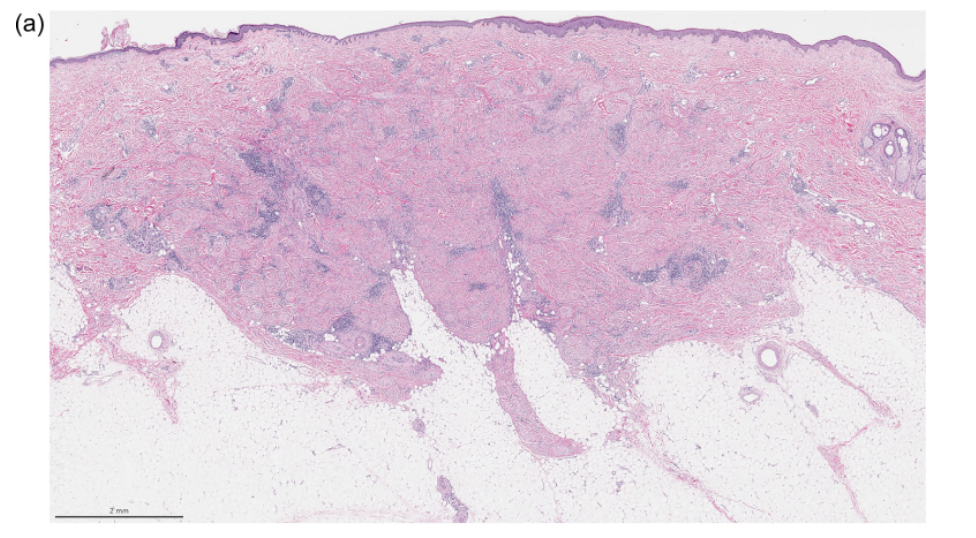

图1.促纤维组织增生型黑色素瘤,单纯型。(A)图示真皮内和皮下有粉染的纤维性区域,伴簇状淋巴细胞;(B)纤维母细胞样梭形黑素细胞,散在于纤维性间质内,周边有簇状淋巴细胞。

单纯型DM中,肿瘤细胞稀疏,也就是说黑素细胞的密度低、大量成分为胶原性间质。黑素细胞主要为散在的孤立性单位,伴纤维母细胞样或神经瘤样特征。上皮样细胞并无簇状表现或致密束状结构。瘤细胞的形态学可相对温和,但至少常见少数细胞核深染、拉长的黑素细胞。核分裂一般难以查见。淋巴细胞簇一般见于真皮网状层的中部至深部、或皮下组织。

单纯型DM